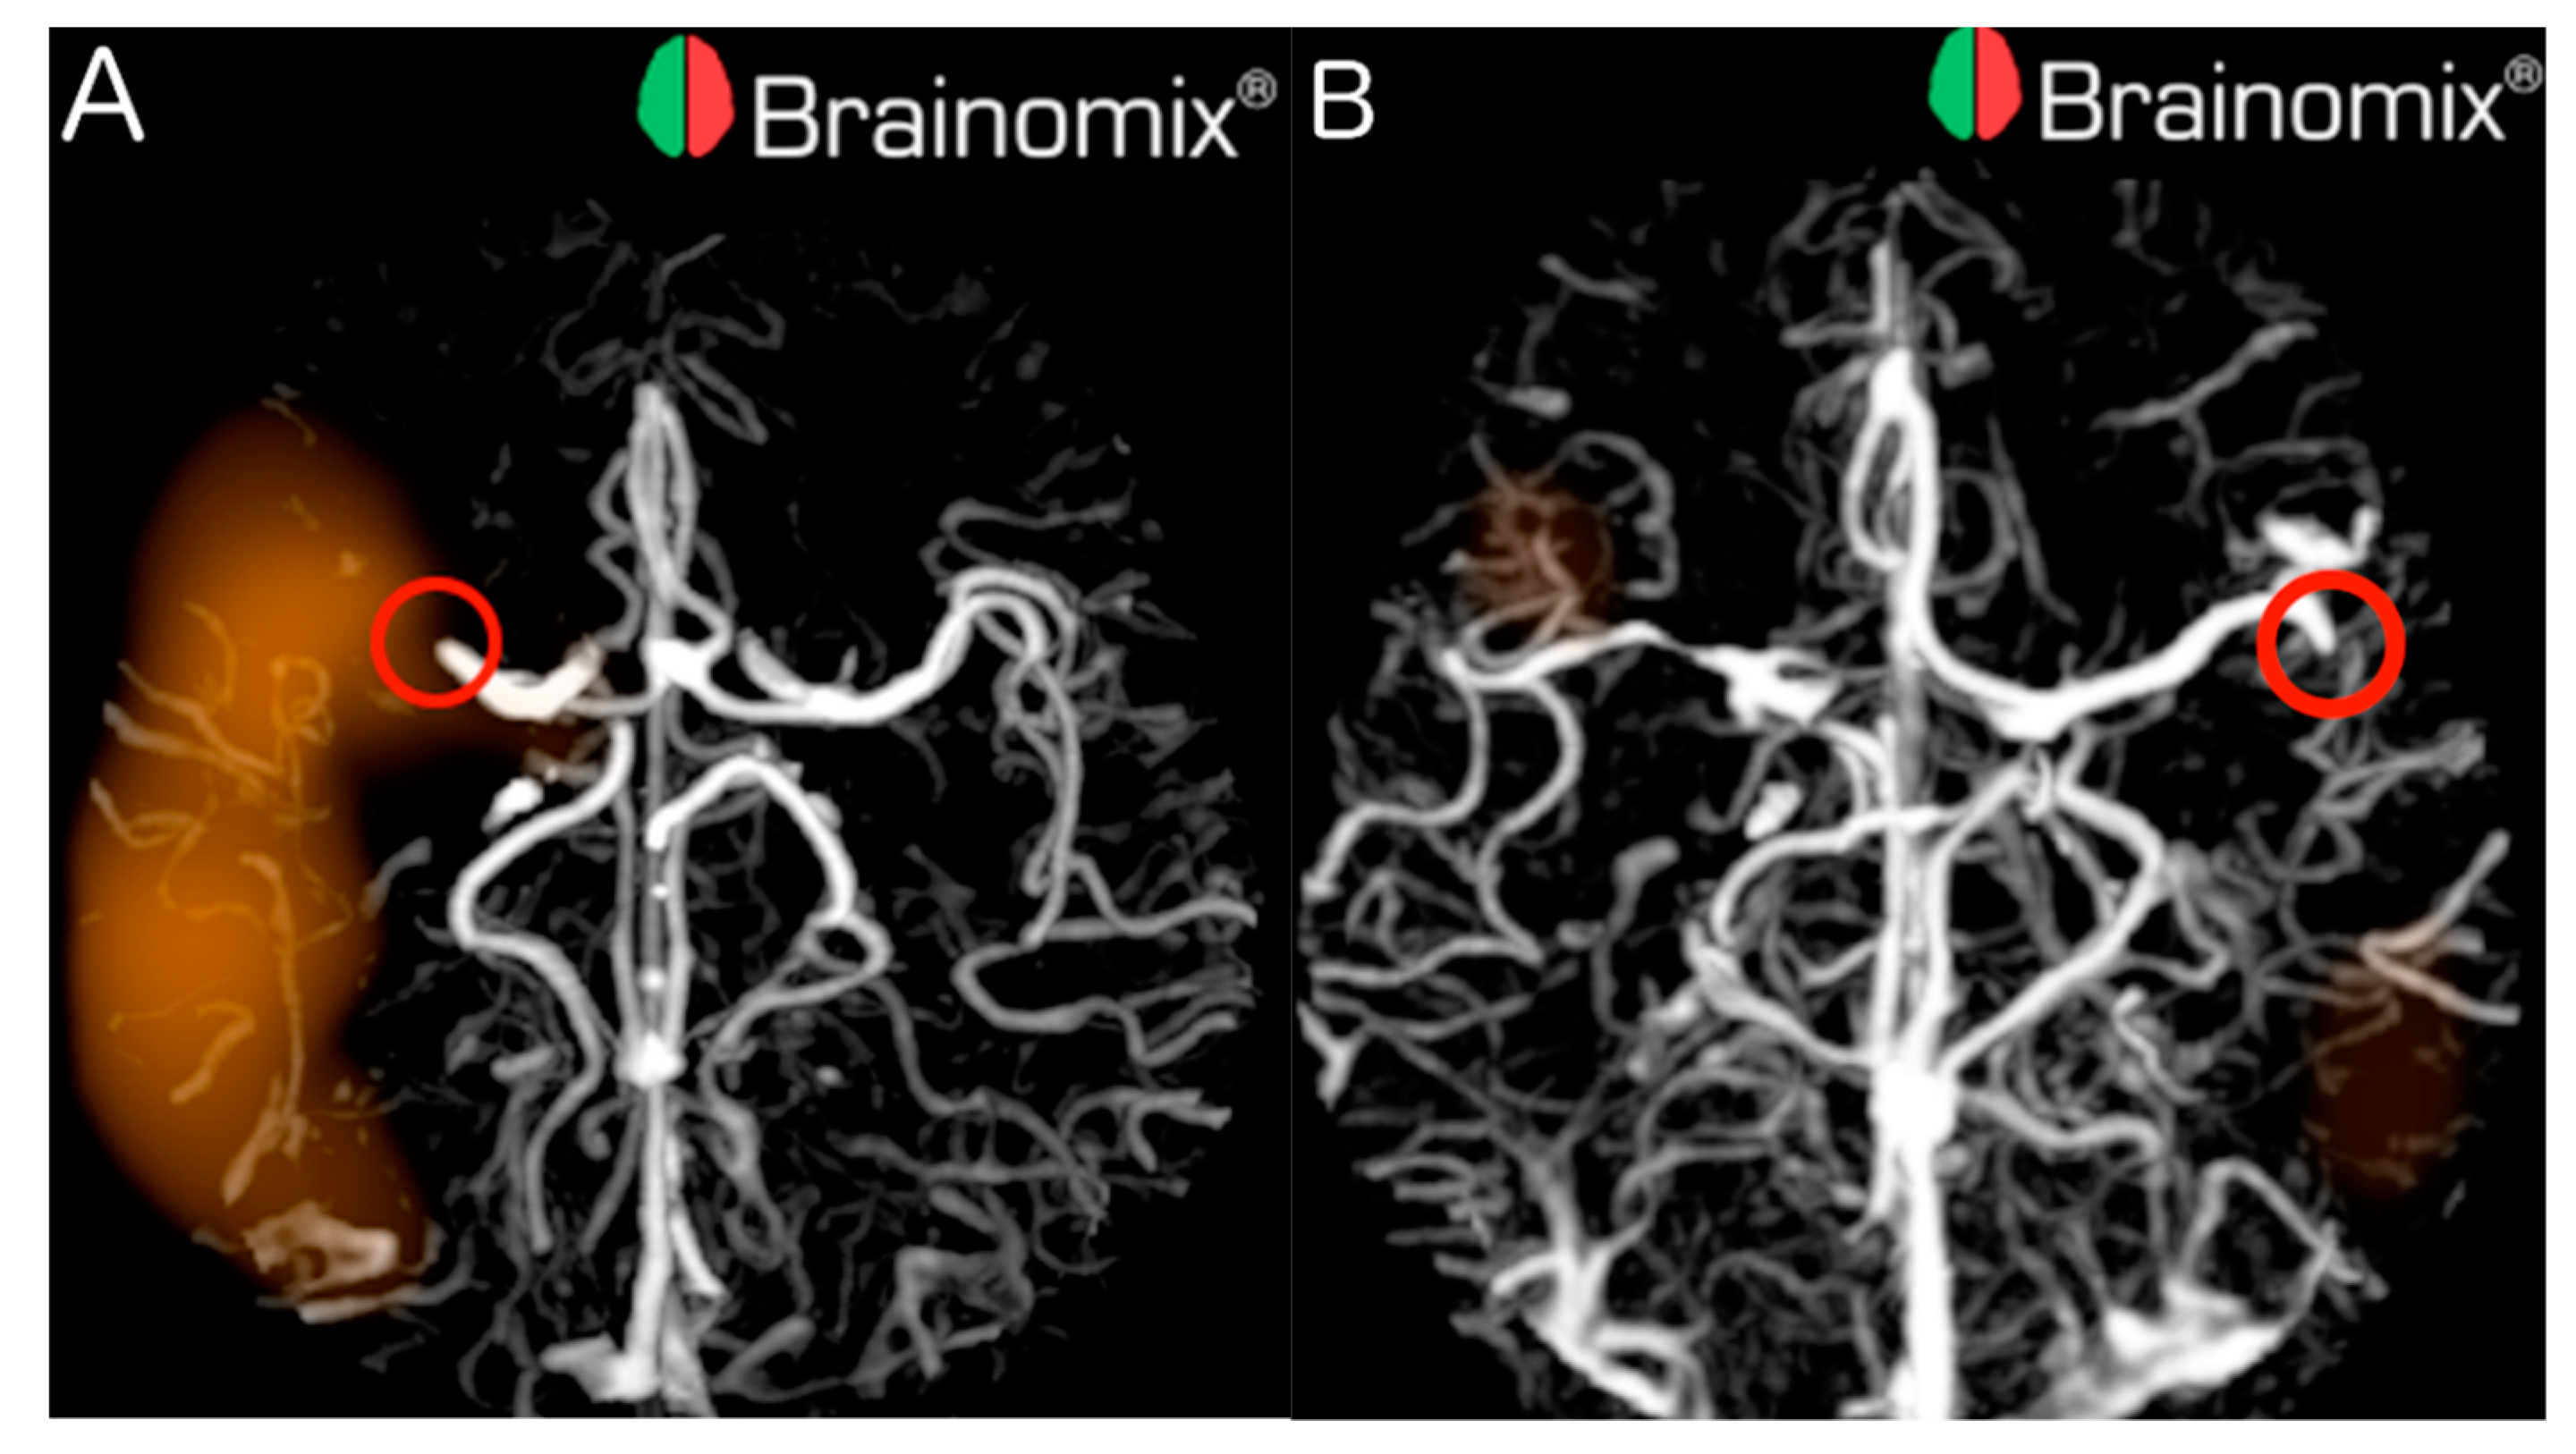

Out of the 70 LVOs, 23 (32.9%) were missed by e-CTA, from which 7 out of 45 (15.6%) were proximal and 16 out of 25 (64.0%) were distal. Examples of proximal and distal LVOs detected by e-CTA are illustrated in Figure 1.

This gave the overall sensitivity for e-CTA of 0.67 (95% CI 0.55–0.78), 0.84 (95% CI 0.71–0.94) for proximal LVOs, and 0.36 (95% CI 0.18–0.57) for distal LVOs. Overall specificity, PPV, NPV and accuracy for e-CTA were 0.95 (95%CI 0.82–0.99), 0.96 (95%CI 0.86–0.99), 0.61 (95%CI 0.47–0.73), and 0.77 (95%CI 0.68–0.84), respectively. The mean processing time was 96 seconds (±23 s).

Figure 1. CTAs of stroke patients with LVOs correctly detected by e-CTA. (A) e-CTA detected proximal LVO of the right MCA-M1 (red circle); (B) e-CTA detected distal LVO of the left MCA-M2 (red circle).